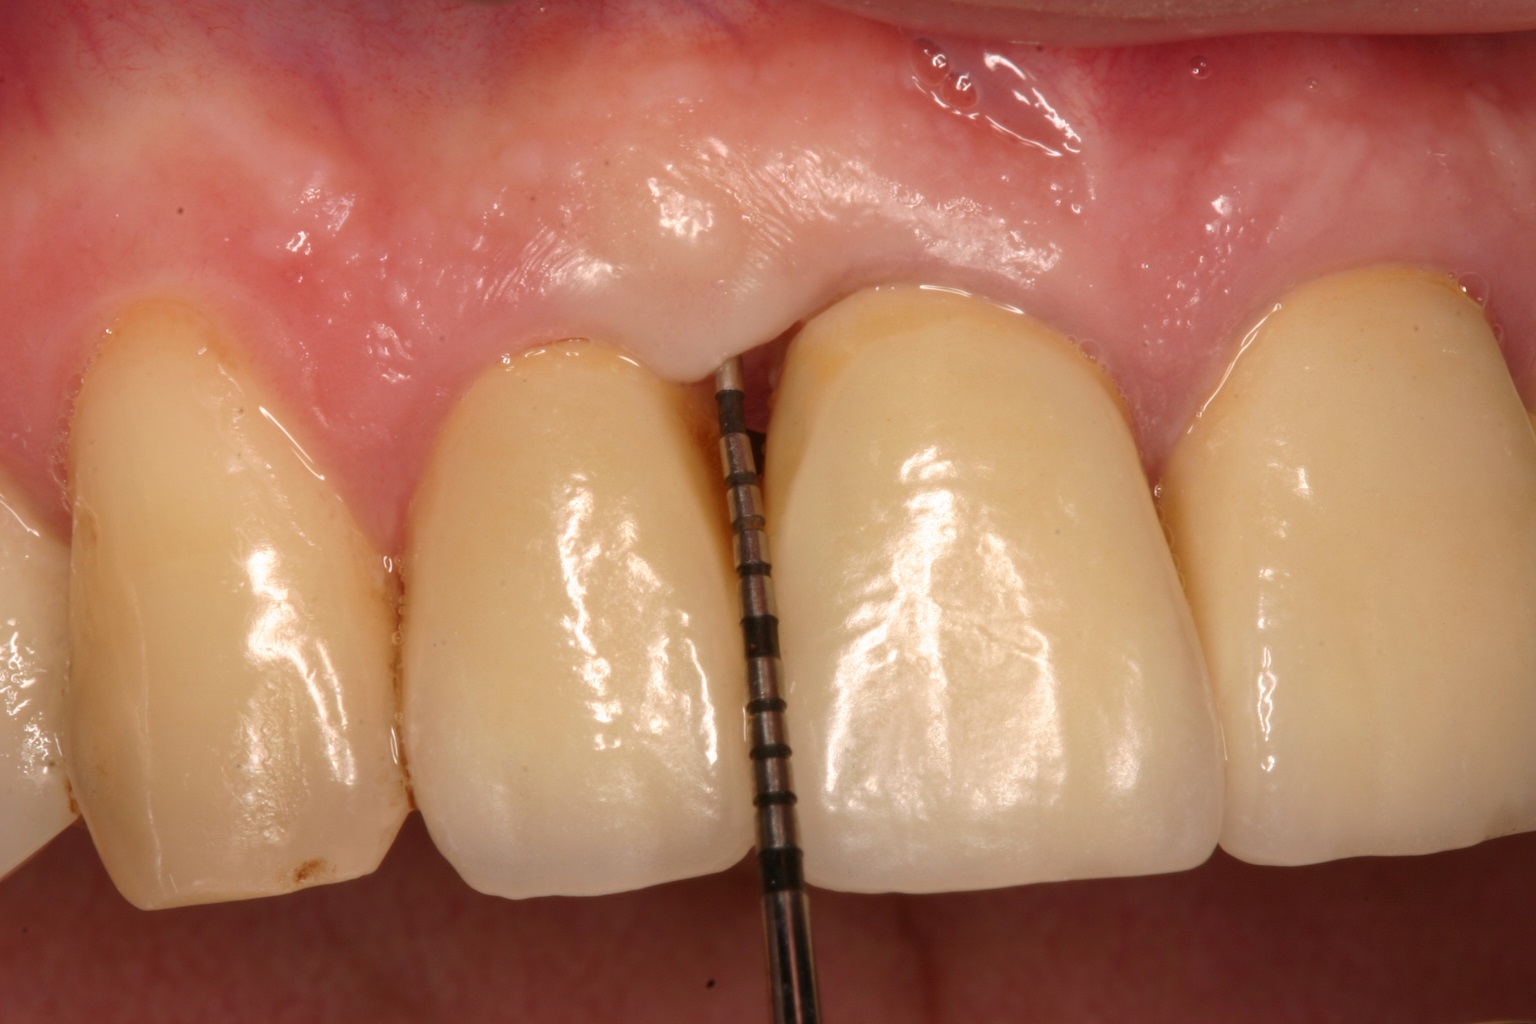

01/08 - Pre-operative probing pocket depth (PPD) at the distal aspect of tooth 11 was 7 mm.Non-contained intrabony defect treated with the simplified papilla preservation flap in conjunction with Straumann® Emdogain® and a particulate bone grafting material - Prof. Dr. Dr. A. Kasaj